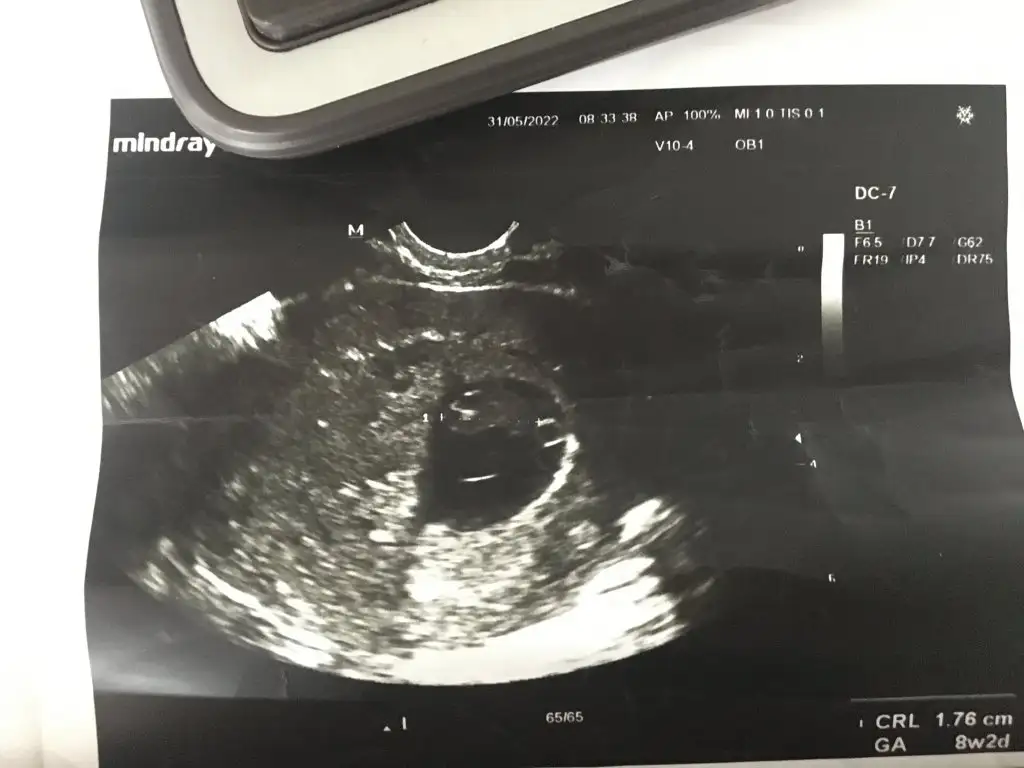

12+0 canım bakabilir misinSelam Kızlarbir çok kişi gruplardan beni bilir. Yine yetiştim imdatlara

prenses gibi12+0 canım bakabilir misin

maalesef yorum yapamadımŞimdi oldu sanırım8+2 vajinal ultrason